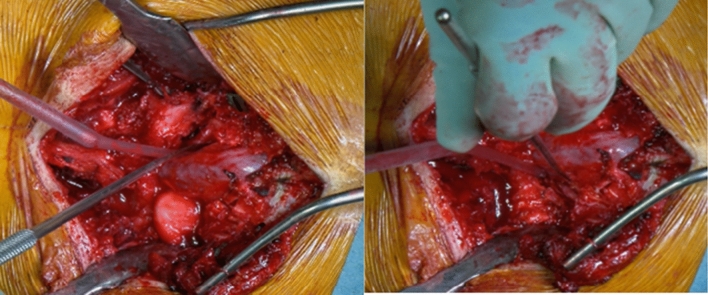

Then, extended L5 laminectomy was performed; care should be taken to remove the inferior facets of L5 and the Gill’s fragment, extending laterally to completely expose the roots. This step is crucial to avoid roots traction during the reduction manoeuvre (Fig. 5).

Fig. 5.

L5 roots were bilaterally exposed